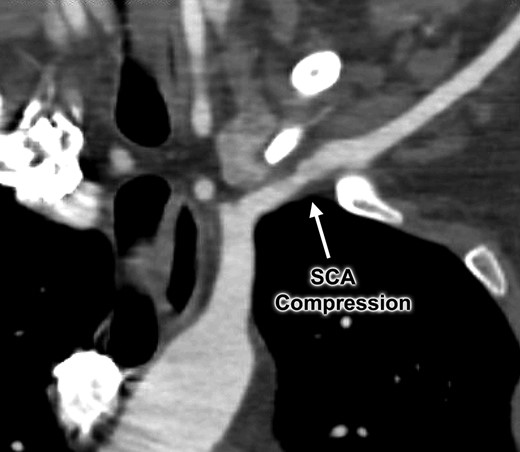

An otherwise healthy 44-year-old female nurse presented with a painful left arm and hand, 2 weeks after she had fallen onto the outstretched left arm while hiking. She sought medical attention when she developed Raynaud’s phenomenon and was unable to feel pulses at the wrist, and clinical evaluation suggested thrombosis of the left brachial, radial and ulnar arteries. Contrast-enhanced computed tomography (Figs 1 and 2) and catheter-based arteriography (Fig. 3) confirmed the diagnosis and showed that while there was no cervical rib or other bony abnormality, there was focal stenosis of the left subclavian artery at the level of the first rib with mild post-stenotic dilatation. These findings indicated that the subclavian artery was the source of thromboembolism and the patient was successfully treated with catheter-based thrombolysis to resolve the acute obstruction. She was discharged on a direct oral anticoagulant but returned within several weeks after recurrence of symptoms. She was found to have rethrombosis and again underwent thrombolysis, followed by anticoagulation with an alternative agent, and was then referred to our specialized TOS center for surgical treatment.

Computed tomography angiogram demonstrating focal area of left subclavian artery (SCA) compression between the first rib and clavicle.